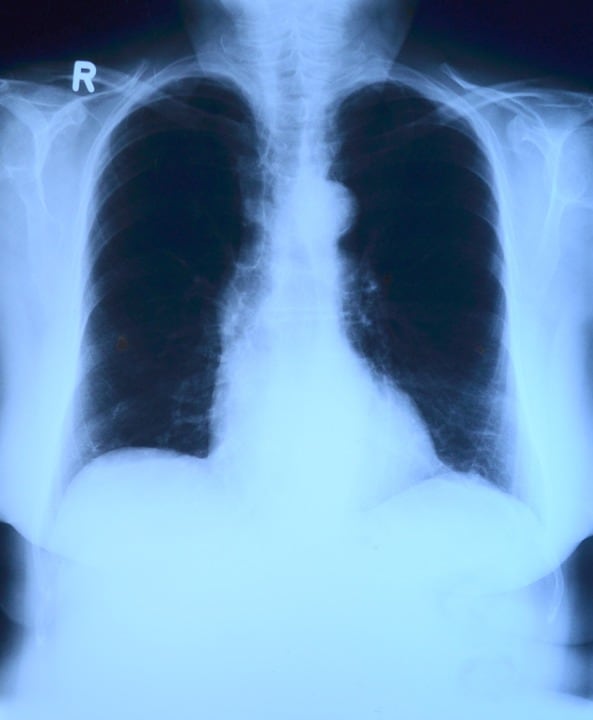

Tras revisar al joven que llegó por un dolor y hacerle una radiografía, los doctores encontraron un cable de carga en su estómago.